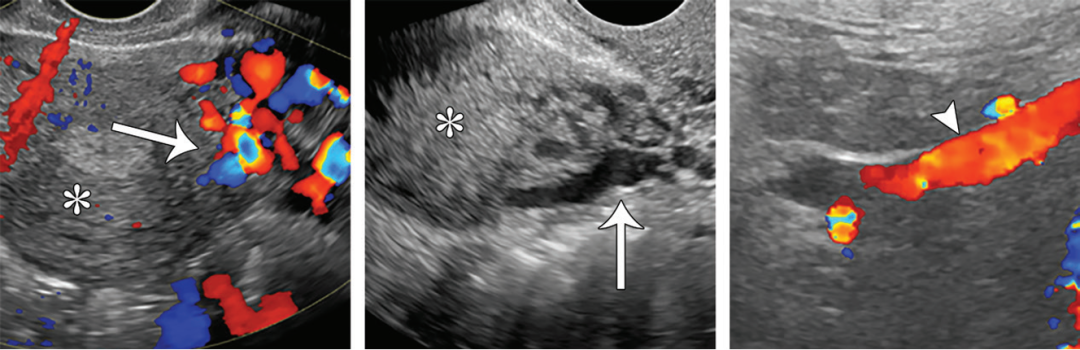

首选筛查:彩色多普勒超声

优势:经济、便捷、无辐射,可动态观察血流方向与速度,尤其擅长经阴道观察深部静脉。行Valsalva动作(屏气增加腹压)可诱发并显示隐匿性反流。

诊断建议标准:

子宫旁静脉直径 > 4 mm

静脉流速 ≤ 3 cm/s

卵巢静脉直径 > 5 mm

子宫肌层静脉扩张

存在多囊卵巢样改变

局限:观察范围有限,难以评估肾静脉水平以上的梗阻(如胡桃夹综合征),无法区分原发与继发性PCS。

图:经腹部斜面多普勒超声图像显示左肾静脉水平左侧卵巢静脉返流 (箭头)